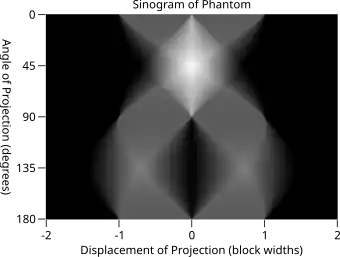

The Radon transform data is often called a sinogram because the Radon transform of an off-center point source is a sinusoid. Consequently, the Radon transform of a number of small objects appears graphically as a number of blurred sine waves with different amplitudes and phases.

Explicit and computationally efficient inversion formulas for the Radon transform and its dual are available. The Radon transform in dimensions can be inverted by the formula:[11] where , and the power of the Laplacian is defined as a pseudo-differential operator if necessary by the Fourier transform: For computational purposes, the power of the Laplacian is commuted with the dual transform to give:[12] where is the Hilbert transform with respect to the s variable. In two dimensions, the operator appears in image processing as a ramp filter.[13] One can prove directly from the Fourier slice theorem and change of variables for integration that for a compactly supported continuous function of two variables: Thus in an image processing context the original image can be recovered from the 'sinogram' data by applying a ramp filter (in the variable) and then back-projecting. As the filtering step can be performed efficiently (for example using digital signal processing techniques) and the back projection step is simply an accumulation of values in the pixels of the image, this results in a highly efficient, and hence widely used, algorithm.